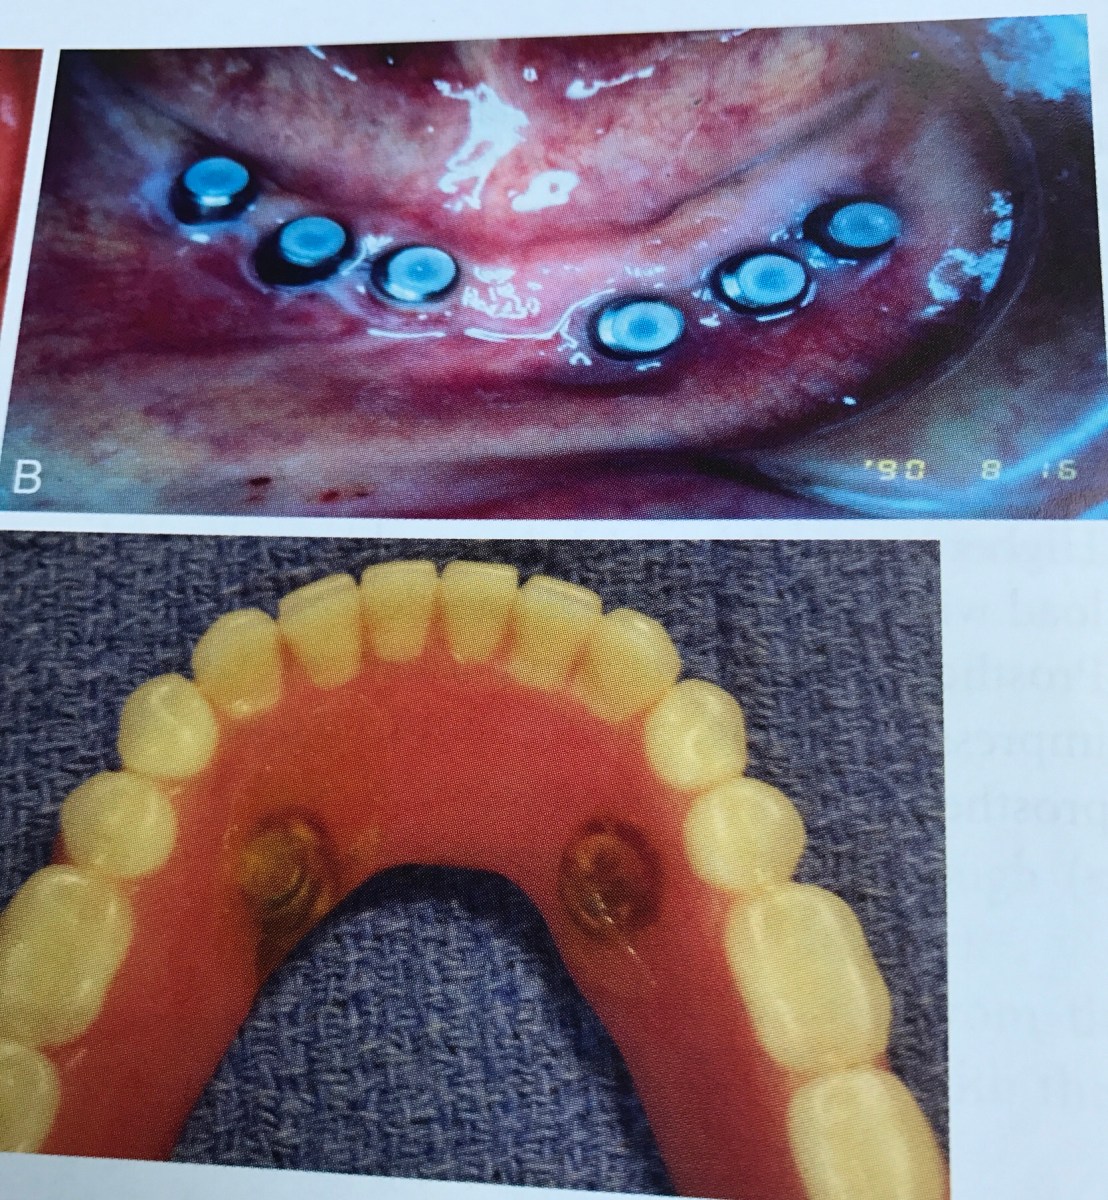

แสดง Ideal Implant placement สำหรับ Removable Prosthesis (Occlusal view)